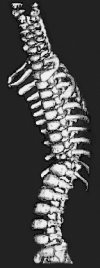

Prior studies have suggested that biomodels enhance patient education, preoperative planning and intra-operative stereotaxy; however, the usefulness of biomodels compared to regular imaging modalities such as X-ray, CT and MR has not been quantified. Our objective was to quantify the surgeon's perceptions on the usefulness of biomodels compared to standard visualisation modalities for preoperative planning and intra-operative anatomical reference. Physical biomodels were manufactured for a series of 26 consecutive patients with complex spinal pathologies using a stereolithographic technique based on CT data. The biomodels were used preoperatively for surgical planning and customising implants, and intra-operatively for anatomical reference. Following surgery, a detailed biomodel utility survey was completed by the surgeons, and informal telephone interviews were conducted with patients. Using biomodels, 21 deformity and 5 tumour cases were performed. Surgeons stated that the anatomical details were better visible on the biomodel than on other imaging modalities in 65% of cases, and exclusively visible on the biomodel in 11% of cases. Preoperative use of the biomodel led to a different decision regarding the choice of osteosynthetic materials used in 52% of cases, and the implantation site of osteosynthetic material in 74% of cases. Surgeons reported that the use of biomodels reduced operating time by a mean of 8% in tumour patients and 22% in deformity procedures. This study supports biomodelling as a useful, and sometimes essential tool in the armamentarium of imaging techniques used for complex spinal surgery.